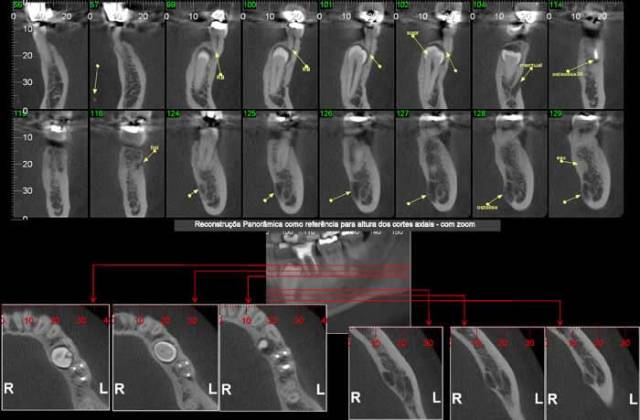

Nos softwares há ferramentas que permitem a reconstrução e a obtenção de novos cortes que mostram imagens de uso pontual na odontologia como os cortes transversais e longitudinais.

Os cortes transversais são cortes perpendiculares ao arco da maxila e mandíbula.

Na reconstrução panorâmica aparece uma régua no limite inferior que serve de localização para os cortes transversais.

Os cortes longitudinais são cortes no sentido vestíbulo lingual ou palatino, perpendiculares a uma reta traçada sobre o dente ou a área em questão.

* Endodontia

Para verificar obturação dos canais radiculares, visualizar canais acessórios, perfurações, reabsorções e avaliação de fraturas radiculares.